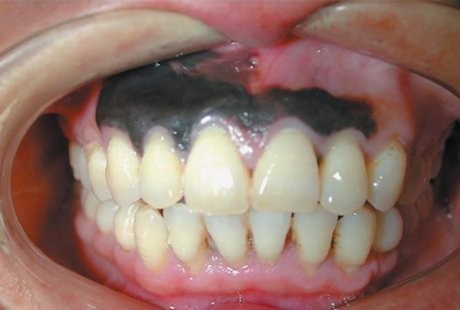

Kena Kanker Langka, Gusi Pria Ini Berubah Jadi Hitam - detikHealth Kamis, 10 Okt 2013 16:35 WIB (Foto: The New England Journal of Medicine) Jakarta - (vit/vit) Infografis Lainnya Infografis Feeding Difficulty Vs Picky Eating, Apa Beda & Dampaknya bagi BB Anak? Infografis Waspadai Dampak Picky Eating pada Anak, Berikut Cara Jitu Cegahnya Infografis Infografis: Strategi dan Formasi Ideal untuk Menang Lomba Balap Bakiak